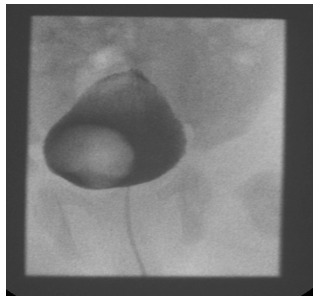

Direct examination during cystoscopy can reveal more than one ureteric orifice on one side and thereby suggest a duplex renal system. MCUG can also reveal ureterocele and is commonly used [Figure 2].

Figure 2: MCUG showing a ureterocele seen as a filling defect on the right side of the urinary bladder. No associated VUR is seen